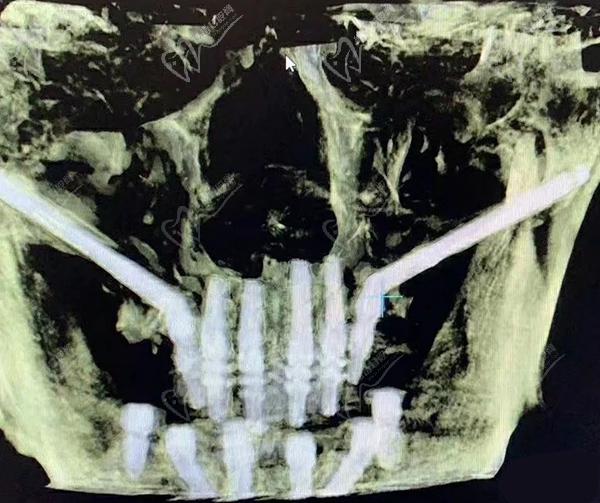

第三步:種植牙

接下來,醫(yī)生會在必要的位置上植入種植體。這些種植體充當(dāng)人工牙根,用于支撐和固定新的牙齒。采用數(shù)字化智能種植技術(shù),上下牙頜各僅需要4-6顆植體就能恢復(fù)半口牙14顆牙齒。

醫(yī)生會進(jìn)行口腔掃描,以獲得足夠的精 確度來制作牙冠。牙冠將在實(shí)驗(yàn)室制作,以匹配患者的牙齒和嘴型。設(shè)有數(shù)字化全息一體牙冠制作中心的正規(guī)口腔醫(yī)院,等在短短2小時內(nèi)就完成牙冠的定制設(shè)計和制作喲。我們將在下面著重討論種植體材料和價格的問題。